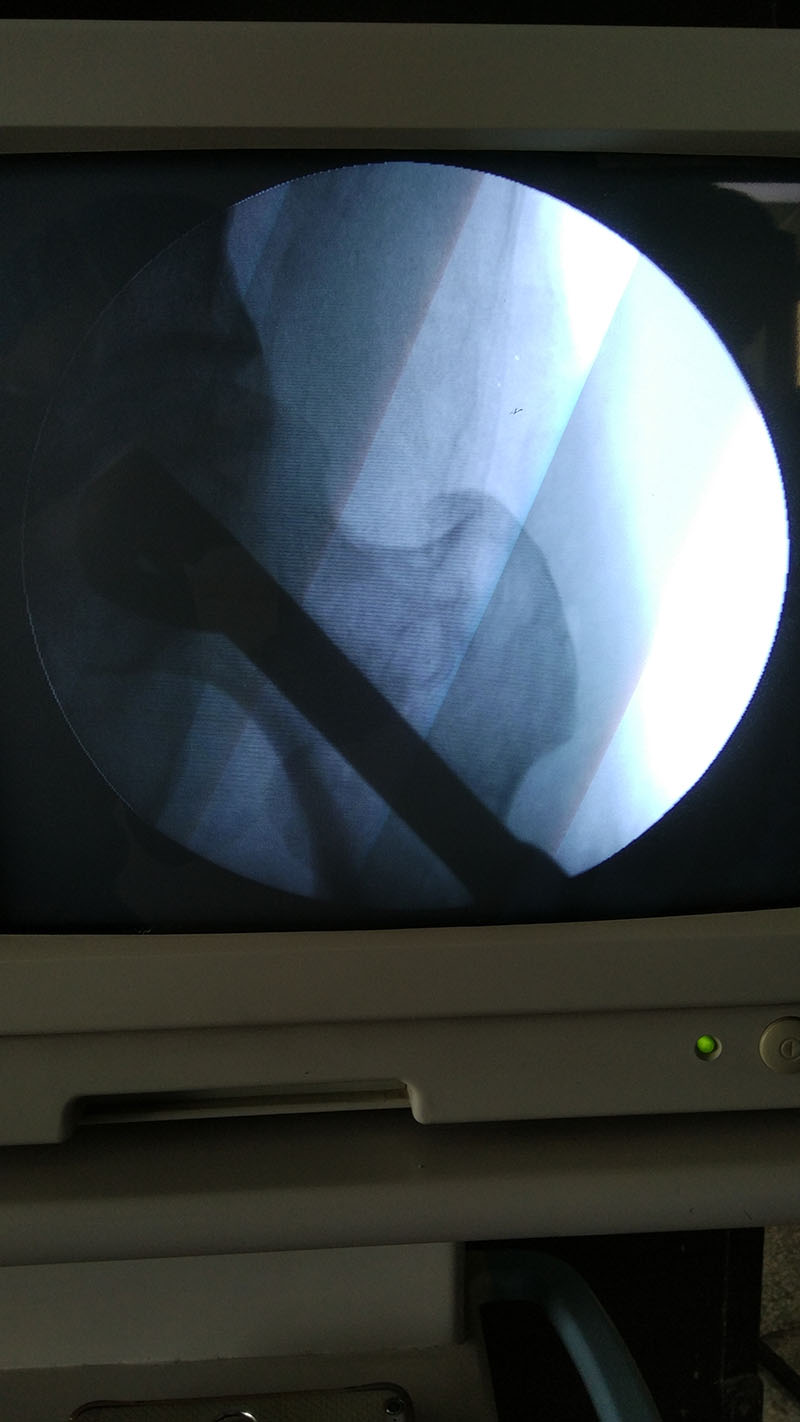

近日,骨一科何光亮主任成功開(kāi)展我院首例股骨頭無(wú)菌性壞死人工陶瓷棒植入術(shù),為我院骨科在骨壞死疾病保髖治療領(lǐng)域邁開(kāi)了新的步伐。

患者劉某,男,52歲,因雙側股骨頭無(wú)菌性壞死1年收住我科。何光亮主任在詳細檢查病人后,結合患者影像學(xué)資料,準確判斷患者屬于股骨頭壞死賓夕法尼亞分期Ib期,處于可以采取保髖治療的階段,在充分與患者及家屬溝通病情后,決定采用人工陶瓷棒技術(shù)進(jìn)行治療。人工陶瓷棒技術(shù)是目前保髖治療手段中的前沿技術(shù),需要醫生對骨壞死分期把握準確,且陶瓷棒技術(shù)屬于微創(chuàng )技術(shù),手術(shù)切口僅2cm,術(shù)中需多次透視以確保器械的精準定位和植入的完美放置。7月8日上午,我科在麻醉科和影像科的配合下,成功為患者進(jìn)行了左側壞死股骨頭的大面積減壓和陶瓷棒植入,術(shù)后麻醉復蘇后,患者即感覺(jué)疼痛的癥狀有明顯緩解,目前患者在進(jìn)一步康復中。